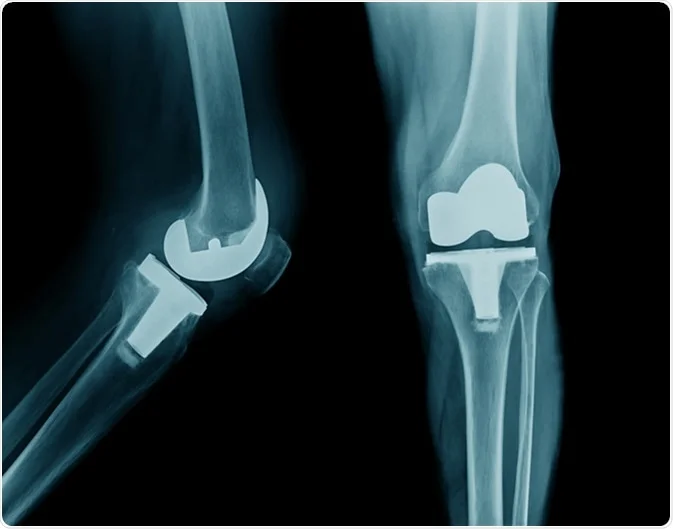

3. Implant Failure

While rare, there is a risk of the prosthetic joint failing. This can be due to issues such as loosening of the implant, wear and tear, or complications from the body rejecting the implant. Symptoms might include persistent pain or instability. Revision surgery may be necessary to address these issues.